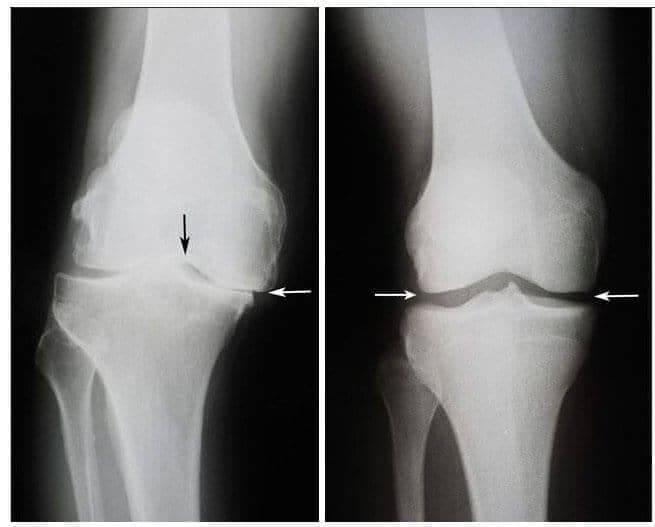

Potom se stal zázrak. Tento specialista navštěvoval Pavlu každý den a dával jí svůj zázračný produkt. Po několika týdnech dokázala vstát z vozíku a chodit k specialistai po svých. O šest týdnů později měla klouby z osteoartritidy vyléčené. Rentgenové snímky to potvrdily.

Vlevo: nímky kolen Pavly Novotné, 75 let. Chrupavková tkáň je zničená, specialista doporučil operaci kolene a náhradu kloubu. Vpravo: snímek pravého kolene Pavly Novotné po užívání produktu Depanten .